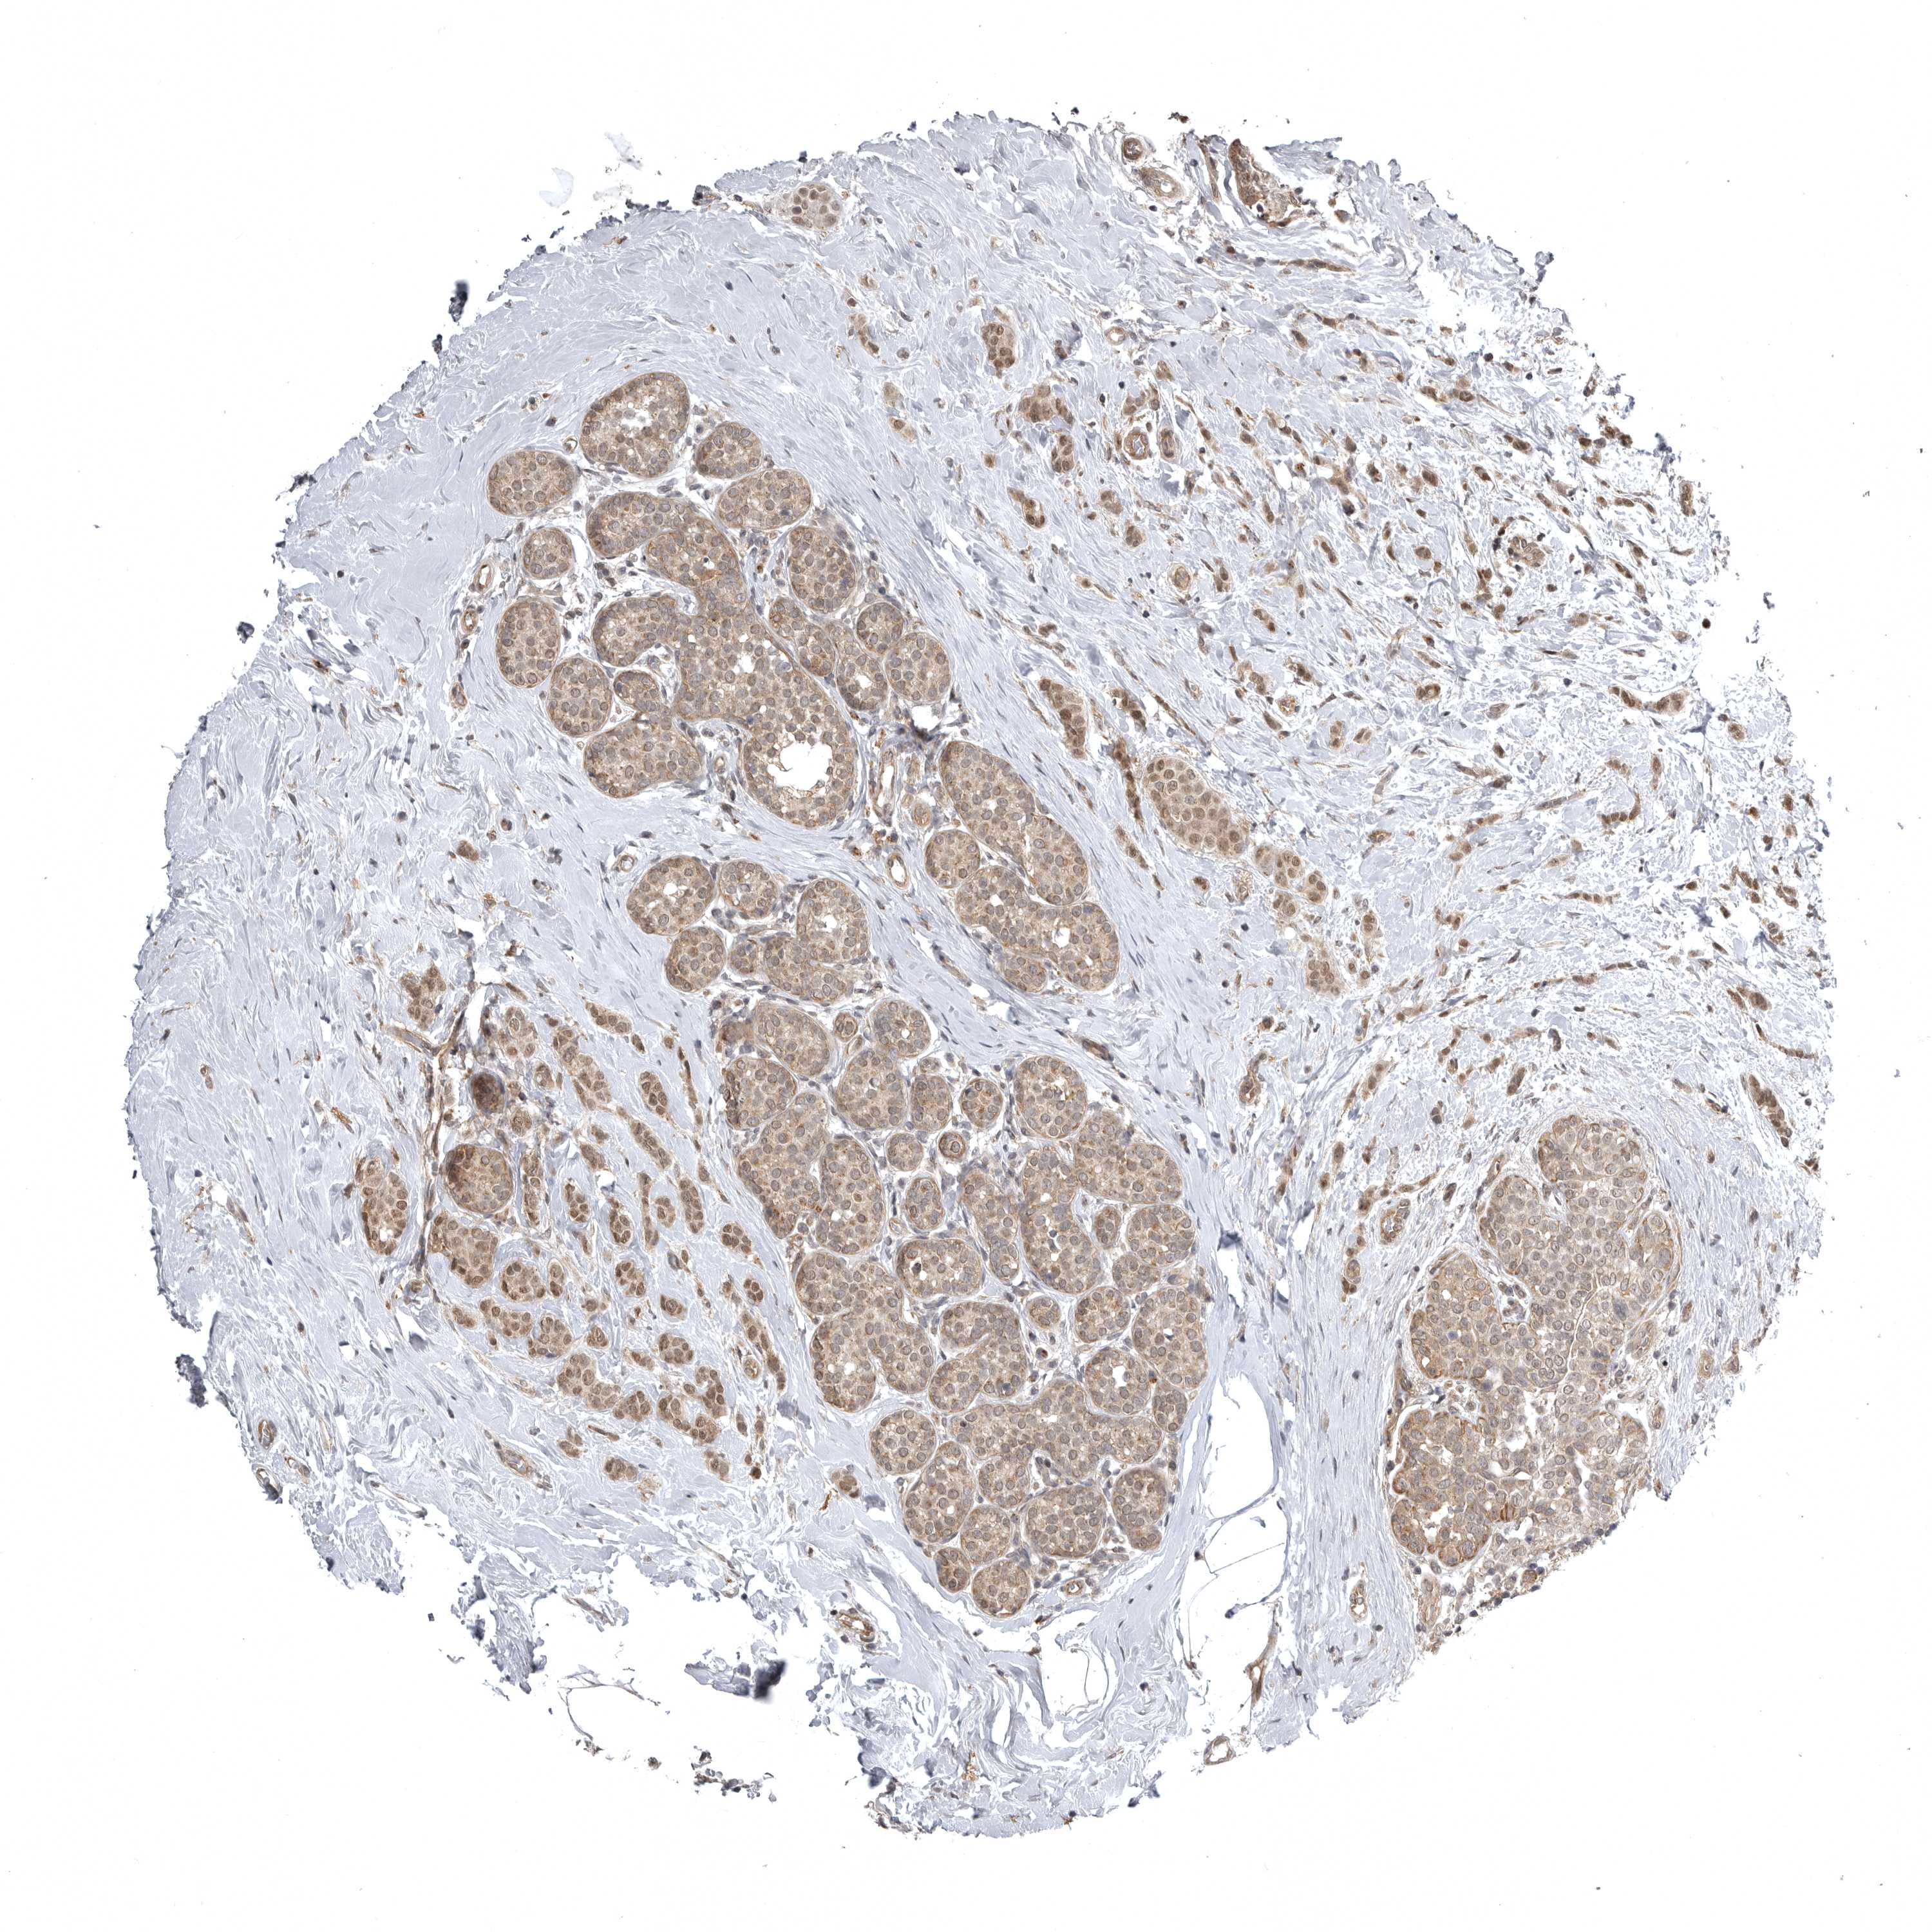

CANCER BREAST CANCER Show tissue menu

BRCA TCGA BRCA VALIDATION PROTEIN EXPRESSION